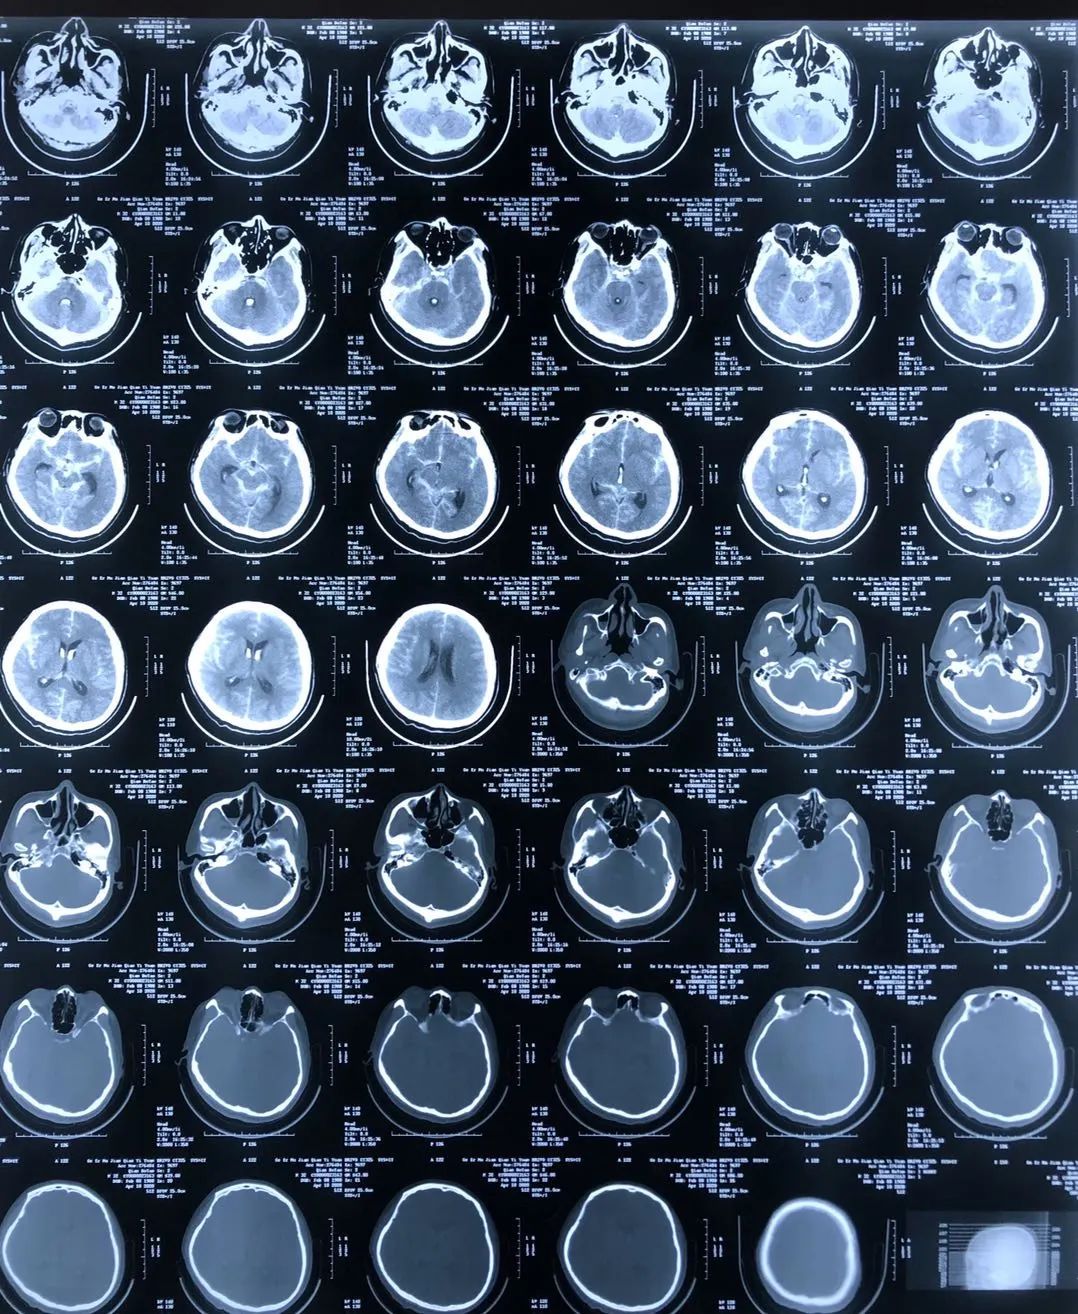

头颅CT提示:蛛网膜下腔出血,药物治疗4天后呼叫青海红十字医院空中医疗救援,我院医护乘救护飞机接回院进一步诊治。

头颅CT

查体:嗜睡状,G.C.S13分,粗测双眼光感,颈抵抗阳性,余无神经系统阳性体征。Hunt-Hess Ⅲ级,改良Fisher分级:4级。眼科查体:双眼玻璃体积血,可及视网膜片状出血。入院急诊在局麻下行DSA,结果示:左侧椎动脉PICA远端夹层动脉。